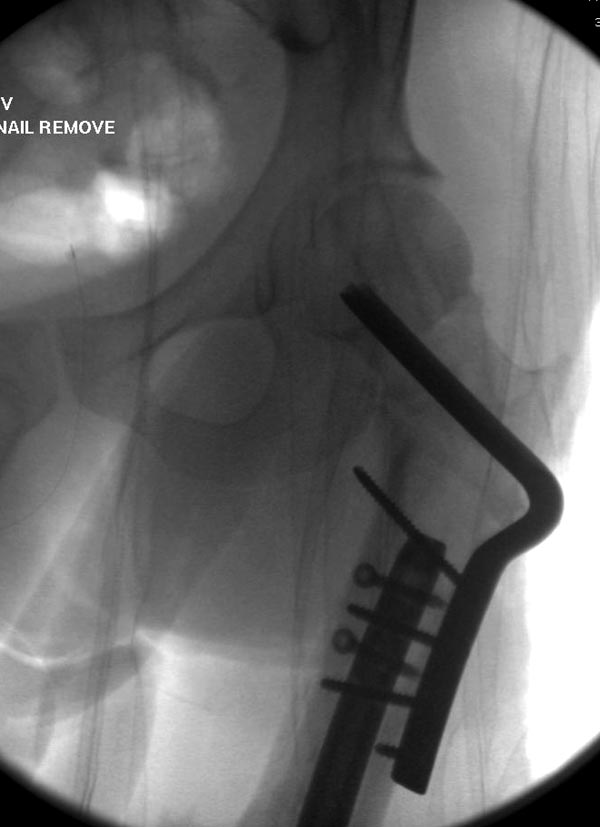

Здесь выставлен ренгенограммы больного, ему 21, травму получил в результате высокоскоростной погони на украденной машине, которая закончилась смертью трех остальных “боевых комрадов”. Начатую коллегой открытую операцию на шейке пришлось закончить мне, установкой винтов и ретроградной фиксацией бедра. Выписка в обычное сроки и наблюдался амбулаторно. Каждый раз напоминали о возможности осложнений ввиде несращения! По истечению 4 месяцев появились признаки варусной деформации. На СТ срезах несращение шейки и бедра. Риминг, замена на более толстый гвоздь и вальгусная остеотомия.

Сразу скажу, что пациент вчера (8.04) прооперирован - артротомия, остеосинтез мыщелков большеберцовой кости канюлированными винтами, открытая репозиция отломков бедренной кости, ретроградный БИОС, остеосинтез надколенника (центральных его отломков) спицами с проволочной петлей. Двухкратная попытка закрытой репозиции шейки на операционном столе после синтеза бедра - абсолютно неэффективна. Учитывая продолжительность и травматичность операции, шейка отложена на 2-й этап. Плечо наверное на 3-й (если вообще делать). Снимки постараюсь предоставить, но чуть позже.